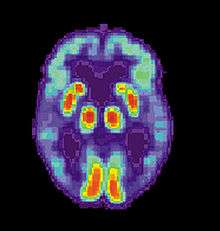

Imaging

Of the many medical imaging techniques available, single photon emission computed tomography (SPECT) appears to be superior in differentiating Alzheimer's disease from other types of dementia, and this has been shown to give a greater level of accuracy compared with mental testing and medical history analysis.[290] Advances have led to the proposal of new diagnostic criteria.[19][109]

PiB PET remains investigational, but a similar PET scanning radiopharmaceutical called florbetapir, containing the longer-lasting radionuclide fluorine-18, has recently been tested as a diagnostic tool in Alzheimer's disease, and given FDA approval for this use.[291][292]